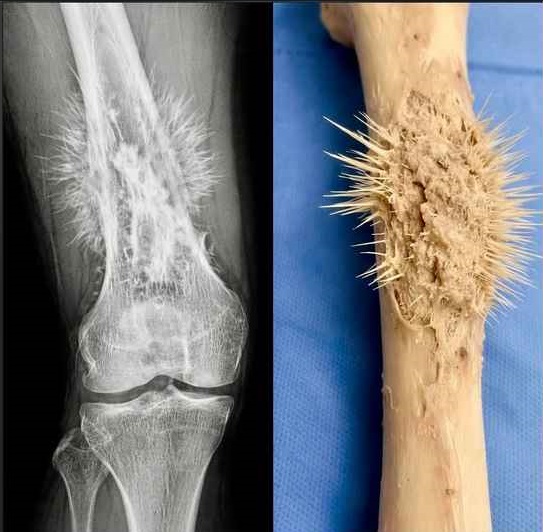

これは、骨に現れる「サンバースト(sunburst)」と呼ばれる所見であり、骨肉腫と呼ばれる悪性骨腫瘍の特徴の一つです。

この所見は、放射状に広がる太陽光線に似ていることから、サンバーストと呼ばれています。これは、腫瘍が急速に増殖し、骨膜(骨を覆う膜)を押し広げ、反応性骨の形成を引き起こすことで現れ、その結果、骨に「棘状」または「棘のような」外観を与えます。

骨肉腫は、原発性骨腫瘍の中で最も頻度が高いものです。一般的に、10代から20代の若年層に発症します。

考えられる症状には、以下のようなものがあります:

徐々に進行し、増強する骨の痛み

骨の周囲の腫れと触知可能な腫瘤

病的骨折(軽微な外傷で生じる骨折)

意図しない体重減少

「腫瘍は急速に増殖し、骨皮質を破って骨膜を隆起させます。これに対し、新しい骨組織が制御不能な形で形成され、放射状かつ不規則な配列を特徴とします。」